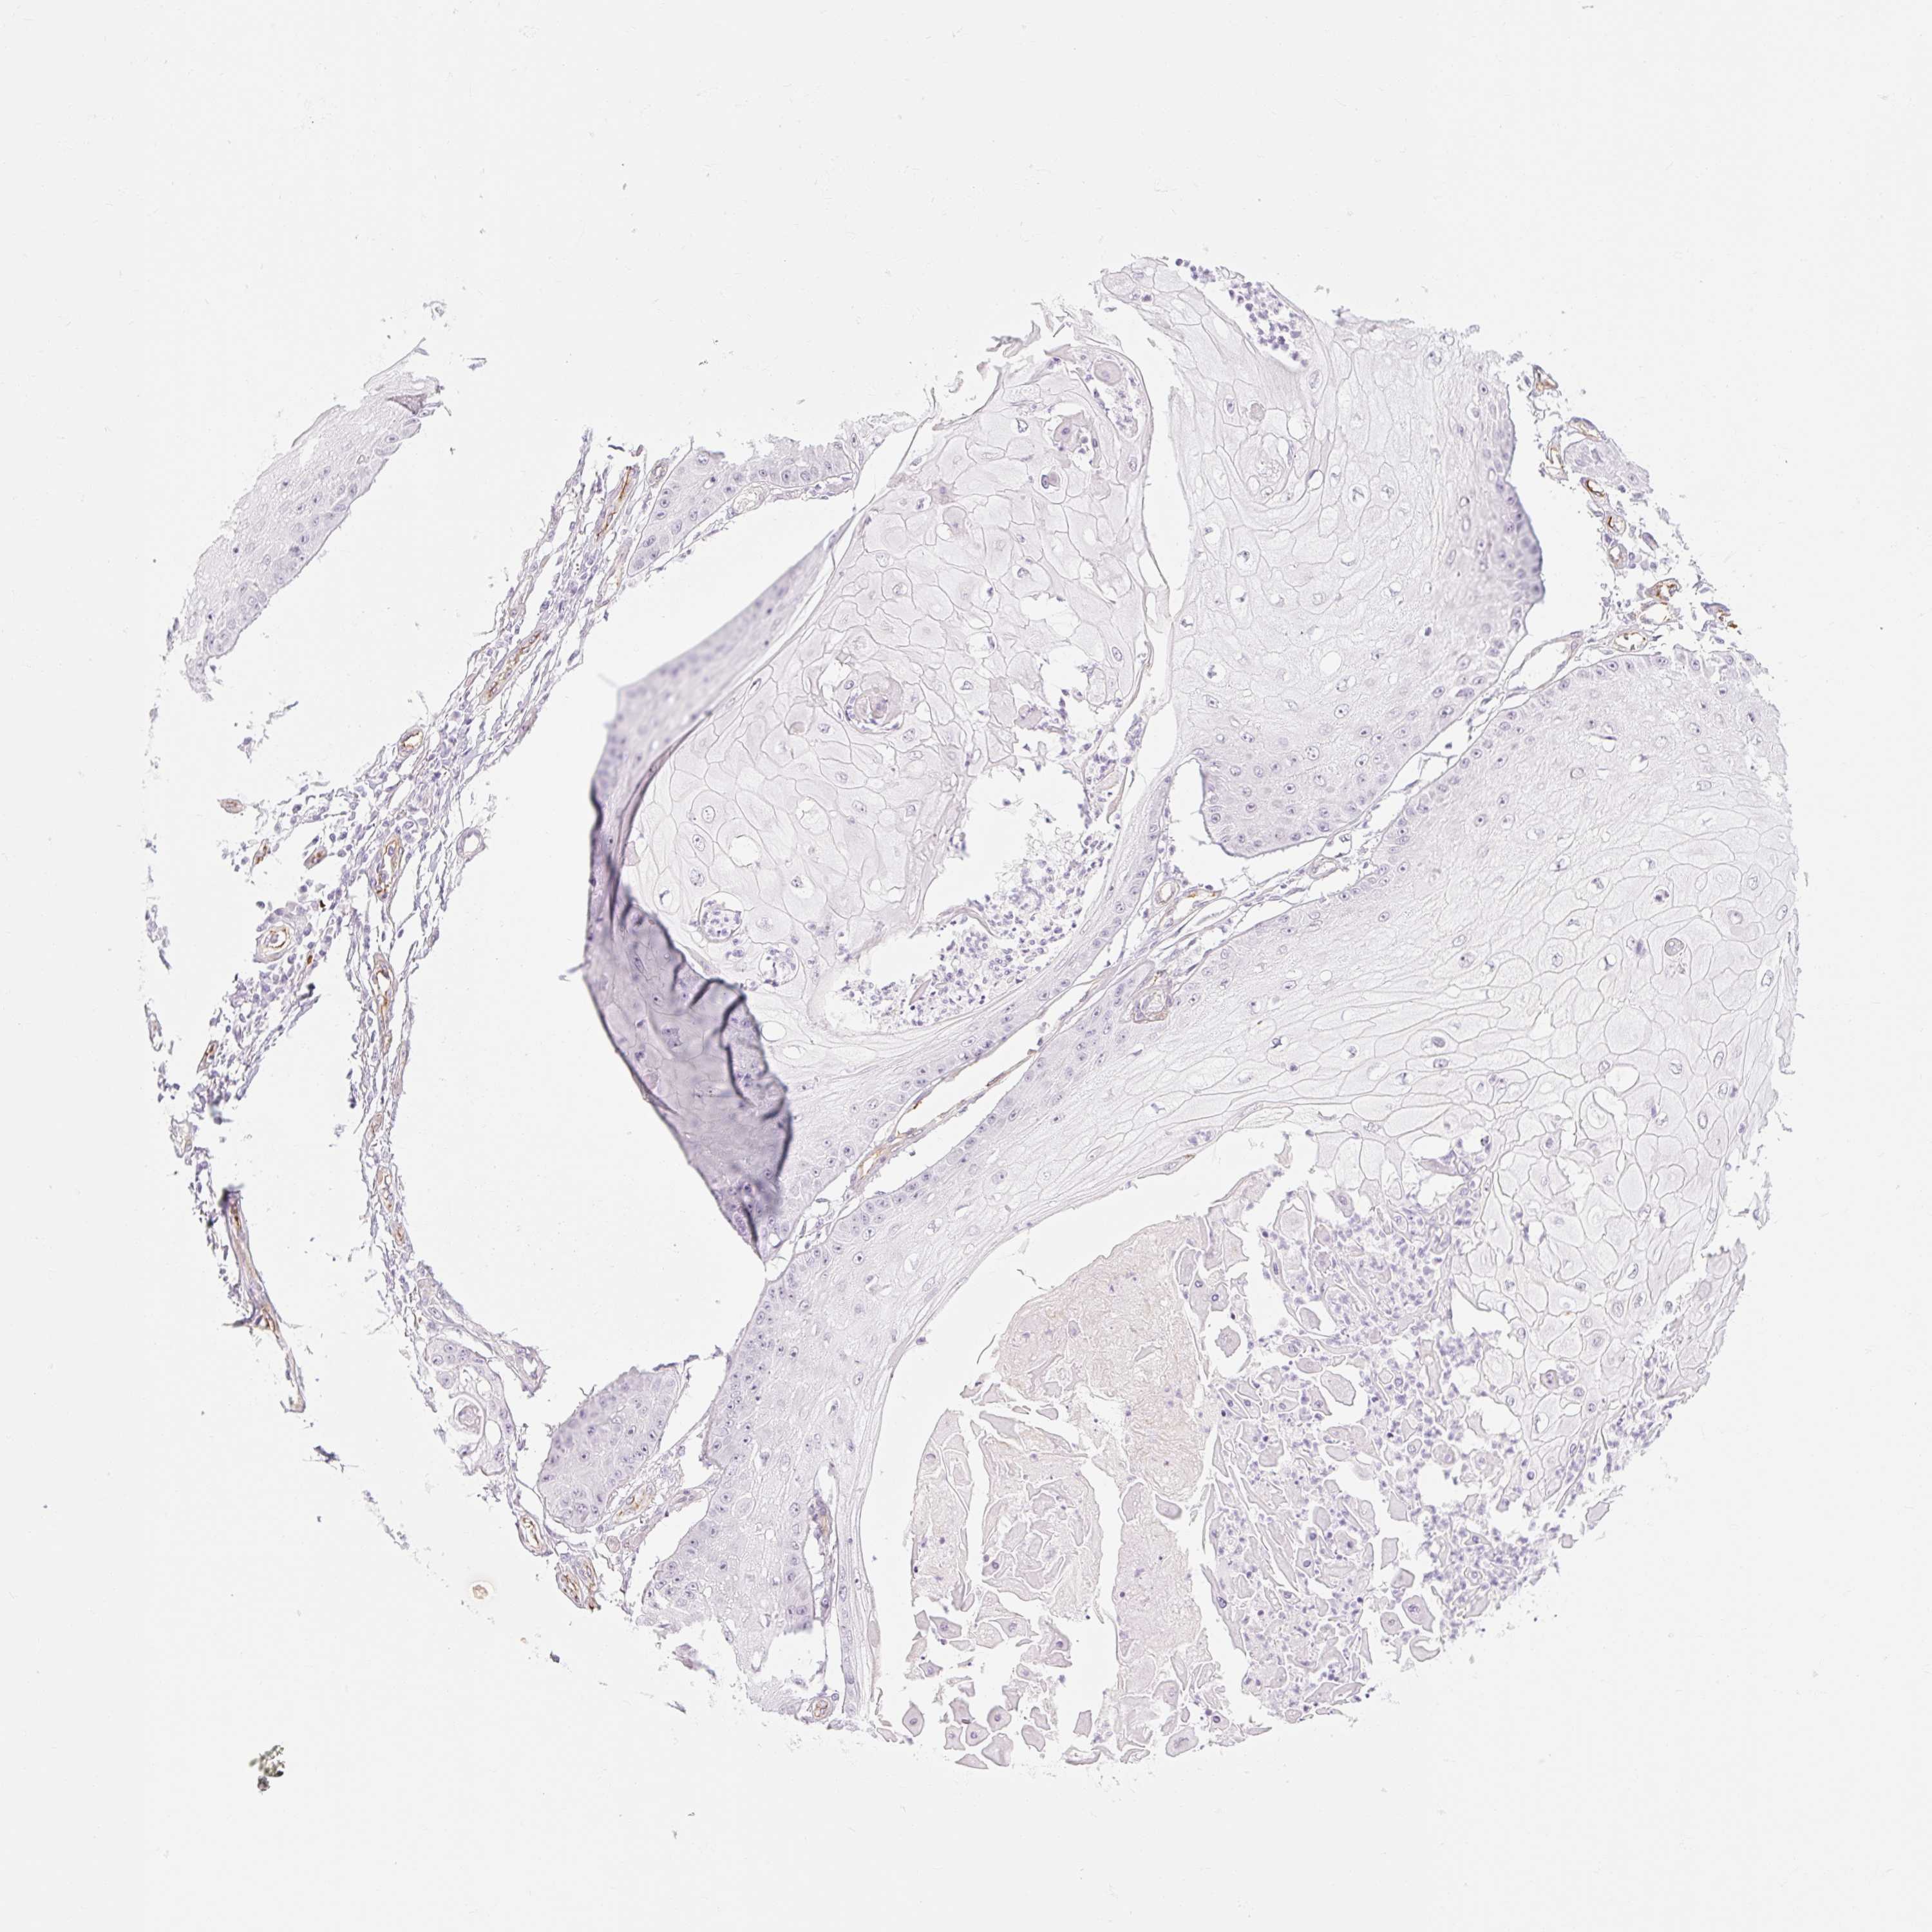

CANCER SKIN CANCER Show tissue menu

Basal cell and squamous cell cancer

SKIN CANCER - Protein expressioni

A mouse-over function shows sample information and annotation data. Click on an image to view it in a full screen mode. Samples can be filtered based on level of antibody staining by selecting one or several of the following categories: high, medium, low and not detected. The assay and annotation is described here.

Each image is clickable and will lead to virtual microscopy that enables deeper exploration of all samples and also displays staining intensity scores, fraction scores and subcellular localization as well as patient and tissue information for each sample.

Antibody HPA056605

Staining

High

Medium

Low

Not detected

Intensity

Strong

Moderate

Weak

Negative

Quantity

>75%

75%-25%

<25%

None

Location

Nuclear

Cytoplasmic/membranous

Cytoplasmic/membranous,nuclear

Basal cell carcinoma

Squamous cell carcinoma, NOS

Squamous cell carcinoma, metastatic, NOS